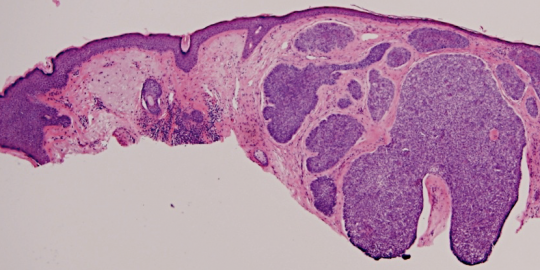

VA54: Left Superior Temple, Basal Cell Carcinoma, Nodular

- * denotes area of liquifactive necrosis with remnant necrotic cell debris